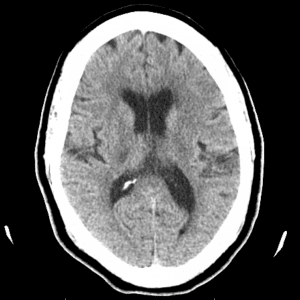

PCA infarct

Case #2